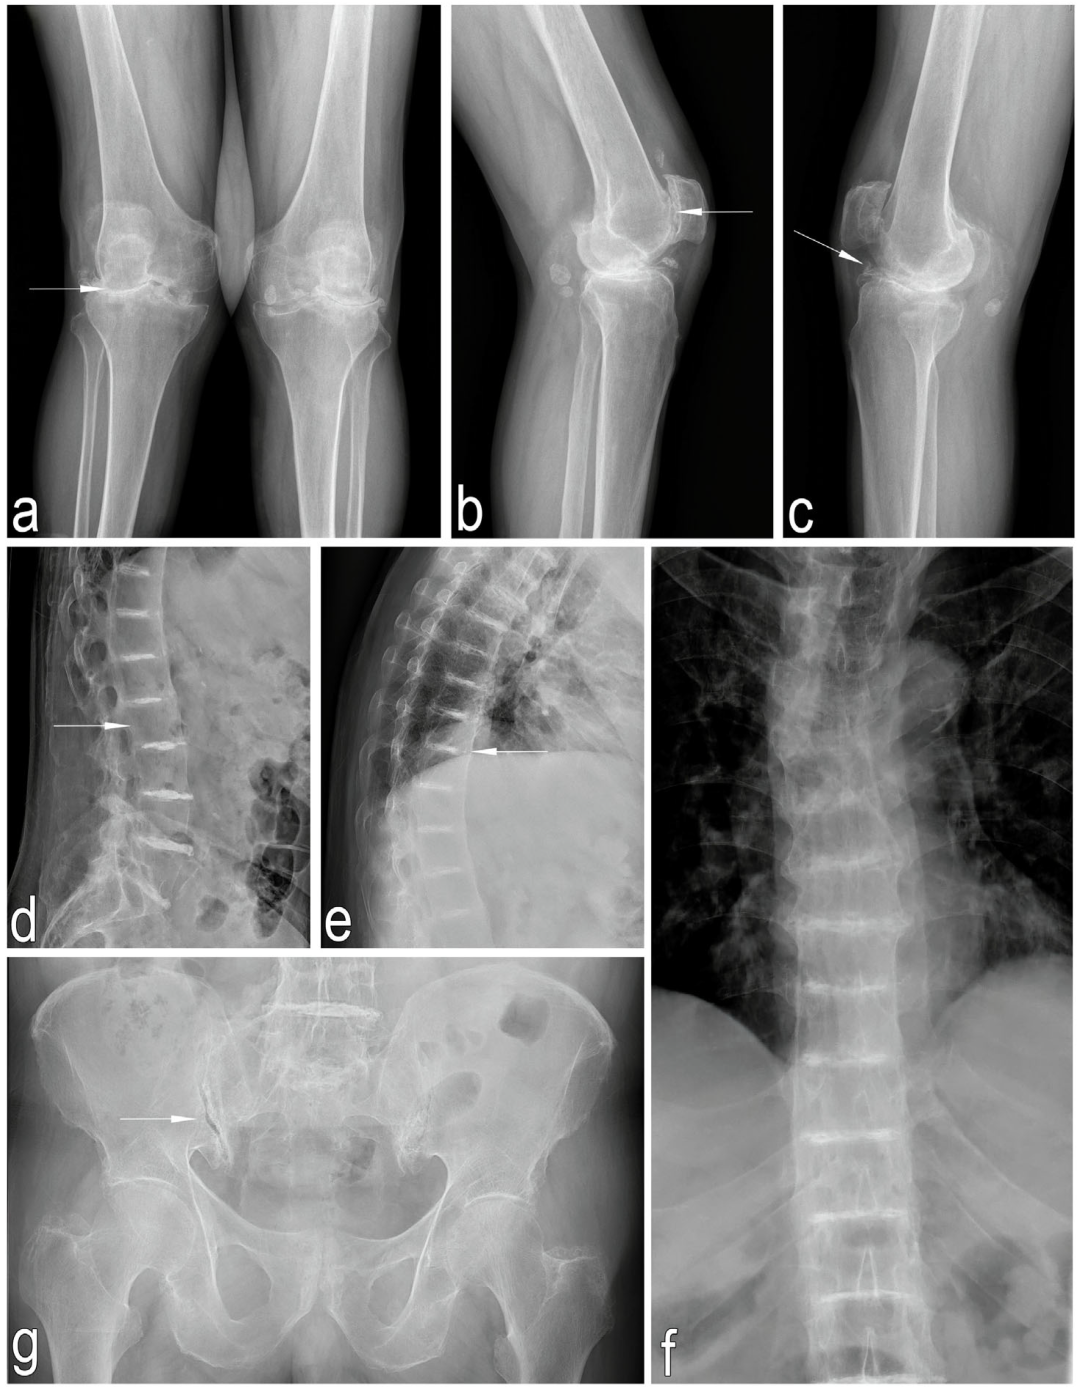

2.1. Before Surgery

2.1.1. Interview and Clinical Examination

2.1.2. Imaging Studies